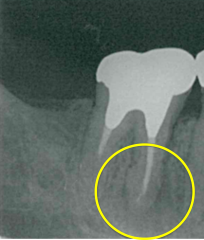

レントゲンでは不明な根尖病巣がCTでははっきり写ります。

同じ患者様です。根管が樋状根になっているのもわかります。